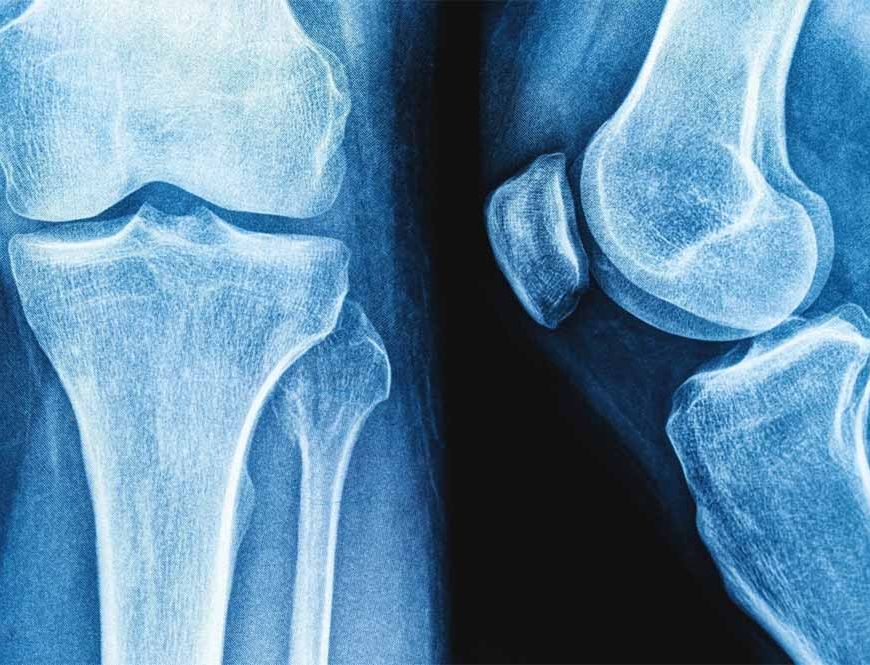

राष्ट्रीय प्रौद्योगिकी संस्थान (एनआईटी) राउरकेला के शोधकर्ताओं ने मानव शरीर में पाई जाने वाली प्राकृतिक शर्करा जैसे अणु हड्डियों के निर्माण और मरम्मत के लिए जिम्मेदार प्रोटीन, बोन मॉर्फोजेनेटिक प्रोटीन-2 के व्यवहार को कैसे प्रभावित कर सकती है? इसका पता लगाया है।

प्रतिष्ठित पत्रिका बायोकैमिस्ट्री में प्रकाशित इस शोध के निष्कर्षों का उपयोग हड्डी और उपास्थि पुनर्जनन के उन्नत उपचार, बेहतर इम्प्लांट और अधिक प्रभावी प्रोटीन-आधारित दवाओं के विकास में किया जा सकता है। प्रोटीन मनुष्य के शरीर में विभिन्न कार्य करते हैं। टिश्यू के निर्माण और रासायनिक प्रतिक्रियाओं में सहयोग देने से लेकर कोशिकाओं के बीच संकेतों के रूप में कार्य करने तक बड़ी जिम्मेदारी निभाते हैं।

हालांकि सर्वोत्तम उत्पादकता के लिए इनका त्रि-आयामी आकृतियों में सटीक मुड़ना या खुलना आवश्यक है। प्रोटीन क्यों और कैसे खुलते हैं? यह समझना जीव विज्ञान का एक प्रमुख लक्ष्य है। इसका प्रभाव चिकित्सा, जैव प्रौद्योगिकी और ड्रग डिलिवरी पर पड़ता है। इस संदर्भ में हड्डी और उपास्थि के निर्माण, चोटों को ठीक करने और स्टेम कोशिकाओं को अस्थि-निर्माण कोशिकाओं में परिणत करने में बीएमपी-2 महत्वपूर्ण भूमिका निभाता है।